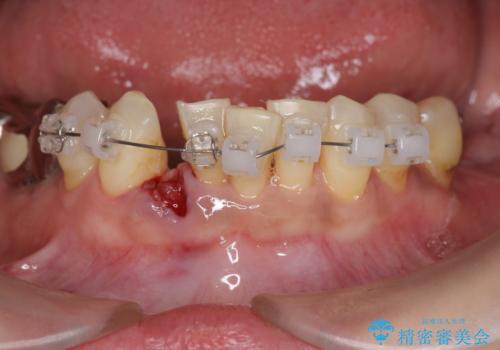

- 残った前歯のほとんどがグラグラし食事ができず、我慢の限界に達し治療を希望され来院されました。

今後しっかりとした食事を楽しめるような咬合機能を回復するために、奥歯はインプラントによる咬合機能回復を行い、前歯は入れ歯で審美性・機能性を回復していきます。

![[インプラントオーバーデンチャー] インプラントで奥歯を支える部分床義歯の治療中](https://seimitsushinbi.jp/wp/wp-content/uploads/2020/05/de21ad4a93f89e2dc7d0d8e465f48ebe-500x350.jpg?v=1590579780)

![[インプラントオーバーデンチャー] インプラントで奥歯を支える部分床義歯の治療中](https://seimitsushinbi.jp/wp/wp-content/uploads/2020/05/b2992fccd5dadda99f93b8e43beb2a13-500x350.jpg?v=1590579802)